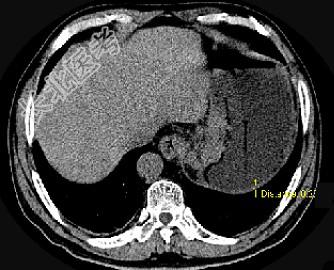

- 单项选择题男,75岁, 吞咽有梗阻感,消瘦、乏力、中上腹痛, 影像检查如图,最可能的诊断是 ( )

A、食管癌

B、胃窦癌

C、贲门癌

D、慢性胃炎

E、胃淋巴瘤